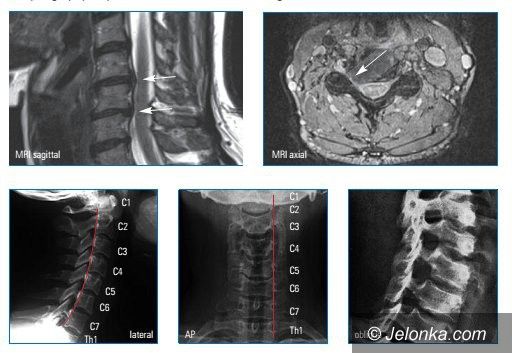

Nowoczesne leczenie małoinwazyjne dyskopatii szyjnej kręgosłupa w KCM

Fot. KCM Clinic SA